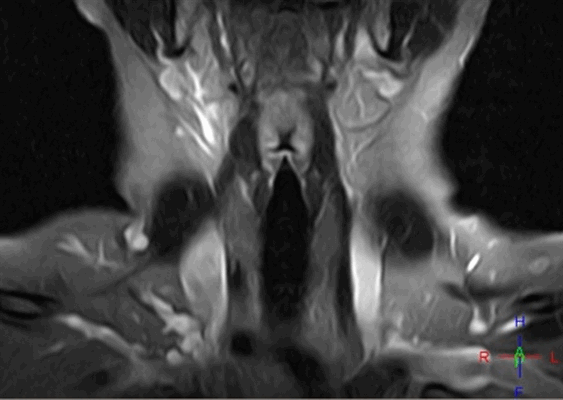

МР-снимок глотки и гортани

Томография показывает особенности строения и патологические изменения органов и тканей, располагающихся на уровне шейного отдела позвоночника:

- глотки;

- гортани;

- трахеи;

- пищевода;

- кровеносных и лимфатических сосудов;

- мышц и сухожилий;

- позвонков;

- спинного мозга и нервов.